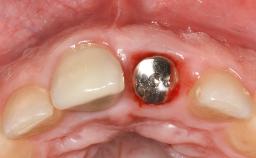

Paolo Casentini demonstrates that peri-implantitis can be successfully treated even at an advanced stage. He discusses a case in which the existing implants and prostheses were both retained while regenerating the defect and creating a band of keratinized tissue. A 69-year-old female patient was referred by her general dentist for evaluation of a recurrent infection at previously placed and restored implants in the posterior left mandible. The patient’s chief complaint was recurrent swelling and pain in the molar region of the left posterior mandible with discomfort during brushing in the same area. The patient reported receiving two implants (36 and 37) nine years earlier.